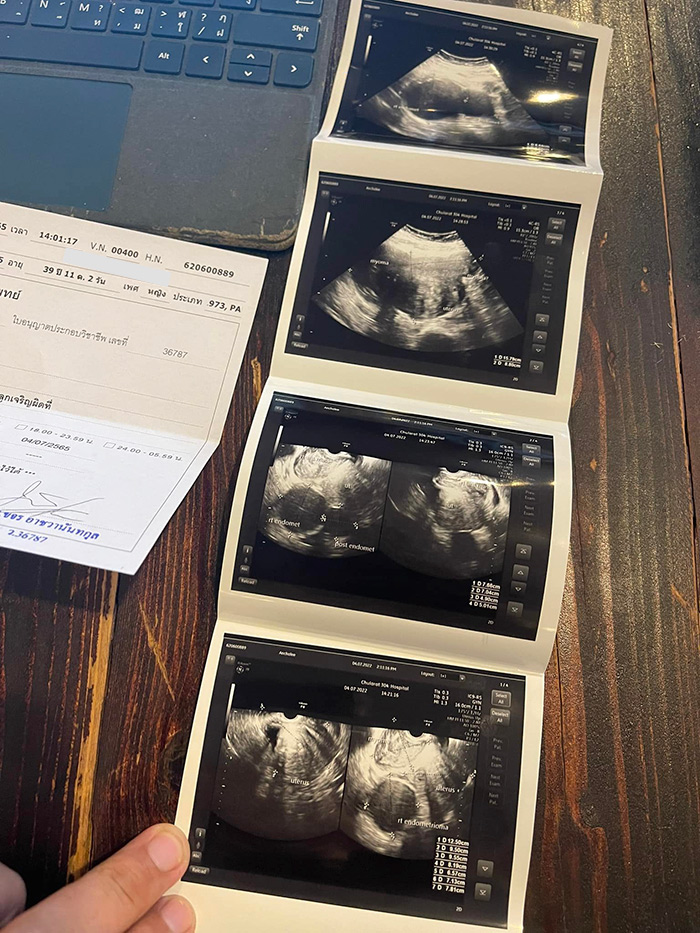

อาการแบบนี้ไม่ปกติแน่นอน หมอจึงตรวจละเอียดขึ้น สิ่งที่พบคือ ช็อคโกแลตซีส, เนื้องอก และถุงน้ำเกาะอยู่กับมดลูกจนบังรังไข่ ต้องผ่าตัดออก

ส่วนอาการปวดที่ก้นเวลาเป็นประจำเดือน สาเหตุมาจากมดลูกที่โตมากกว่าคนปกติ 2 เท่า คนทั่วไปประมาณ 5-7 เซนติเมตร แต่ของคุณเปิ้ล 15 เซนติเมตร ซึ่งนี่คือสิ่งที่น่าห่วงที่สุด

ภาพจาก เฟซบุ๊ก Manoch Chae Kub